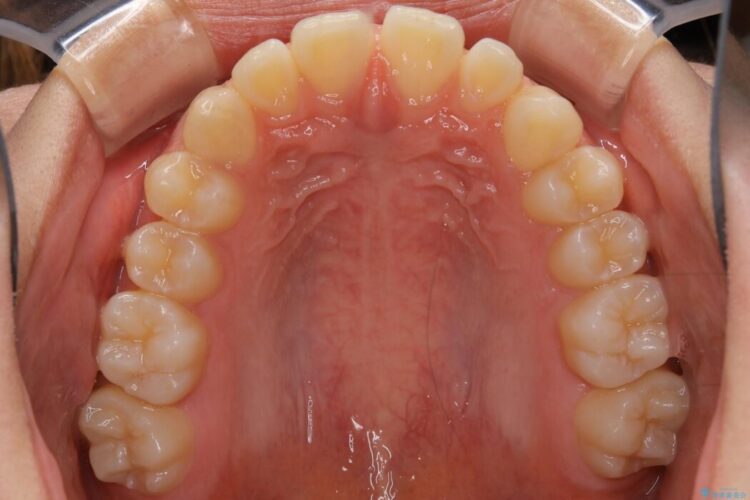

すきっ歯を改善したいとご来院された患者様です。

インビザライン・クリンチェック(シミュレーション)を行い、インビザラインライトで治せる範囲であると診断し、矯正治療を行いました。

マウスピース14枚・期間4ヶ月で主訴であるすきっ歯を改善し、治療を終えることが出来ました。